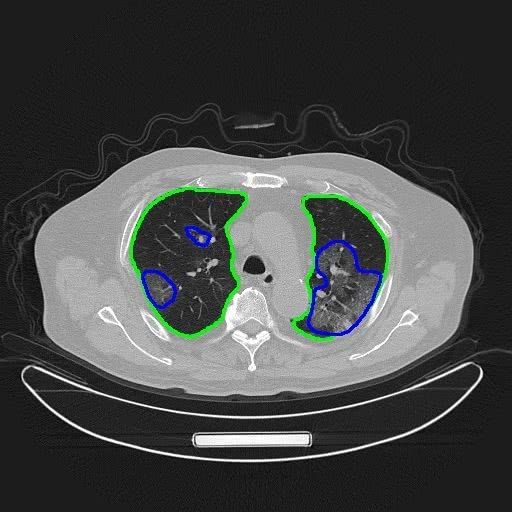

按照一次胸部CT产生300张影像计算,医生肉眼阅片将耗费5-15分钟。而AI与人工协作的方式,由AI技术分割出可能的病灶图像区域,提示医生重点查看(如下图),将大幅提升检查效率,减轻医生工作量,并让患者得到更及时的治疗。

(AI对CT图像进行自动分割:绿色圈是肺部,蓝色圈是新冠肺炎病灶)